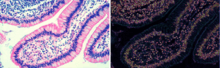

Phase stretch transform (PST) is a computational approach to signal and image processing. One of its utilities is for feature detection and classification.[1][2] PST is related to time stretch dispersive Fourier transform.[3] It transforms the image by emulating propagation through a diffractive medium with engineered 3D dispersive property (refractive index). The operation relies on symmetry of the dispersion profile and can be understood in terms of dispersive eigenfunctions or stretch modes.[4] PST performs similar functionality as phase contrast microscopy but on digital images. PST is also applicable to digital images as well as temporal, time series, data.

Here the principle is described in the context of feature enhancement in digital images. The image is first filtered with a spatial kernel followed by application of a nonlinear frequency-dependent phase. The output of the transform is the phase in the spatial domain. The main step is the 2-D phase function which is typically applied in the frequency domain. The amount of phase applied to the image is frequency dependent with higher amount of phase applied to higher frequency features of the image. Since sharp transitions, such as edges and corners, contain higher frequencies, PST emphasizes the edge information. Features can be further enhanced by applying thresholding and morphological operations. PST is related to warped (anamorphic) stretch transform, another computational algorithm inspired by optical physics and one that performs nonuniform sampling and sparse coding.

PST has been used for edge detection in biomedical images and synthetic aperture radar (SAR) image processing.[5][6]